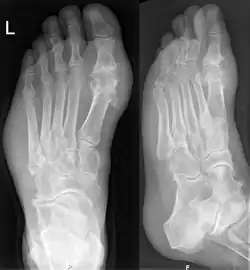

Gout may be diagnosed and treated without further investigations in someone with hyperuricemia and the classic acute arthritis of the base of the great toe (known as podagra). Synovial fluid analysis should be done if the diagnosis is in doubt.[17][51] Plain X-rays are usually normal and are not useful for confirming a diagnosis of early gout.[5] They may show signs of chronic gout, such as bone erosion.[47]